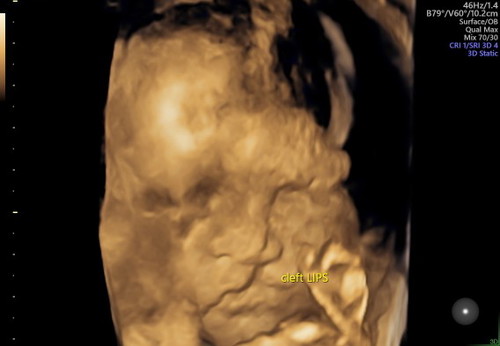

Assalamualaikum para bunda ... Semoga kalian sehat selalu yaa ๐ Entah harus mulai dari mana aku cerita ... Kemarin aku USG dan denger kabar bahwa anak kami di diagnosis cacat (cleft lip) / bibir sumbing ... Seperti cambuk yang teramat sakit dengar berita seperti ini ... Ini ujian untuk aku dan suamiku ... dan aku tidak mau kalah dengan keadaan ini ... Aku terima semua ujian ini dengan ikhlas dan penuh syukur ... Karena semua ini sudah Allah tetapkan untuk kami ... Mudah"an Allah mengangkat derajat kami dari semua ujian ini ... Tentu nya semoga dunia dan seisi nya yang bertemu dengan seseorang yang tidak sempurna fisik nya seperti anak kami bisa menghargai bahwa mereka tetap karunia Allah ... Karena tentu nya mereka butuh pelukan bukan hinaan ... Do'akan kami kuat dan sabar ya para bunda ... Dan do'akan kami sebagai org tua agar bisa merubah nasib anak kami ke yang lebih baik aamiin ... ๐

Baca lagiPas bunda USG di 27 weeks apakah sudah d konfirmasi di Dr fertomaternal atau (maaf) USG biasa ? Soalnya saya sudah konfirm ke 2 Dr yang USG biasa ... Dan saya check lagi ke DR fertomaternal ... Jadi sudah 3x check dan benar adanya bahwa anak saya d diagnosis cleft lip ... Apakah ada harapan buat saya bunda nanti si baby bisa sempurna d dalam kandungan meskipun sudah d diagnosis seperti itu ???? ๐ฅบ๐ฅบ